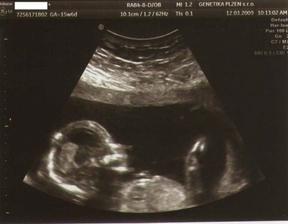

11.3.09 - KO dopadla výborně, miminko opět v akci,všechny orgány OK, srdíčko tluče

12.3.09 - AMNIO na Genetice v Plzni- nic příjemnýho, ale vydržet se to dalo, viděli jsme s tatínkem všechny orgány podrobně a hlavně: už víme pohlaví našeho vytouženého miminka:

je to HOLČIČKA !!!